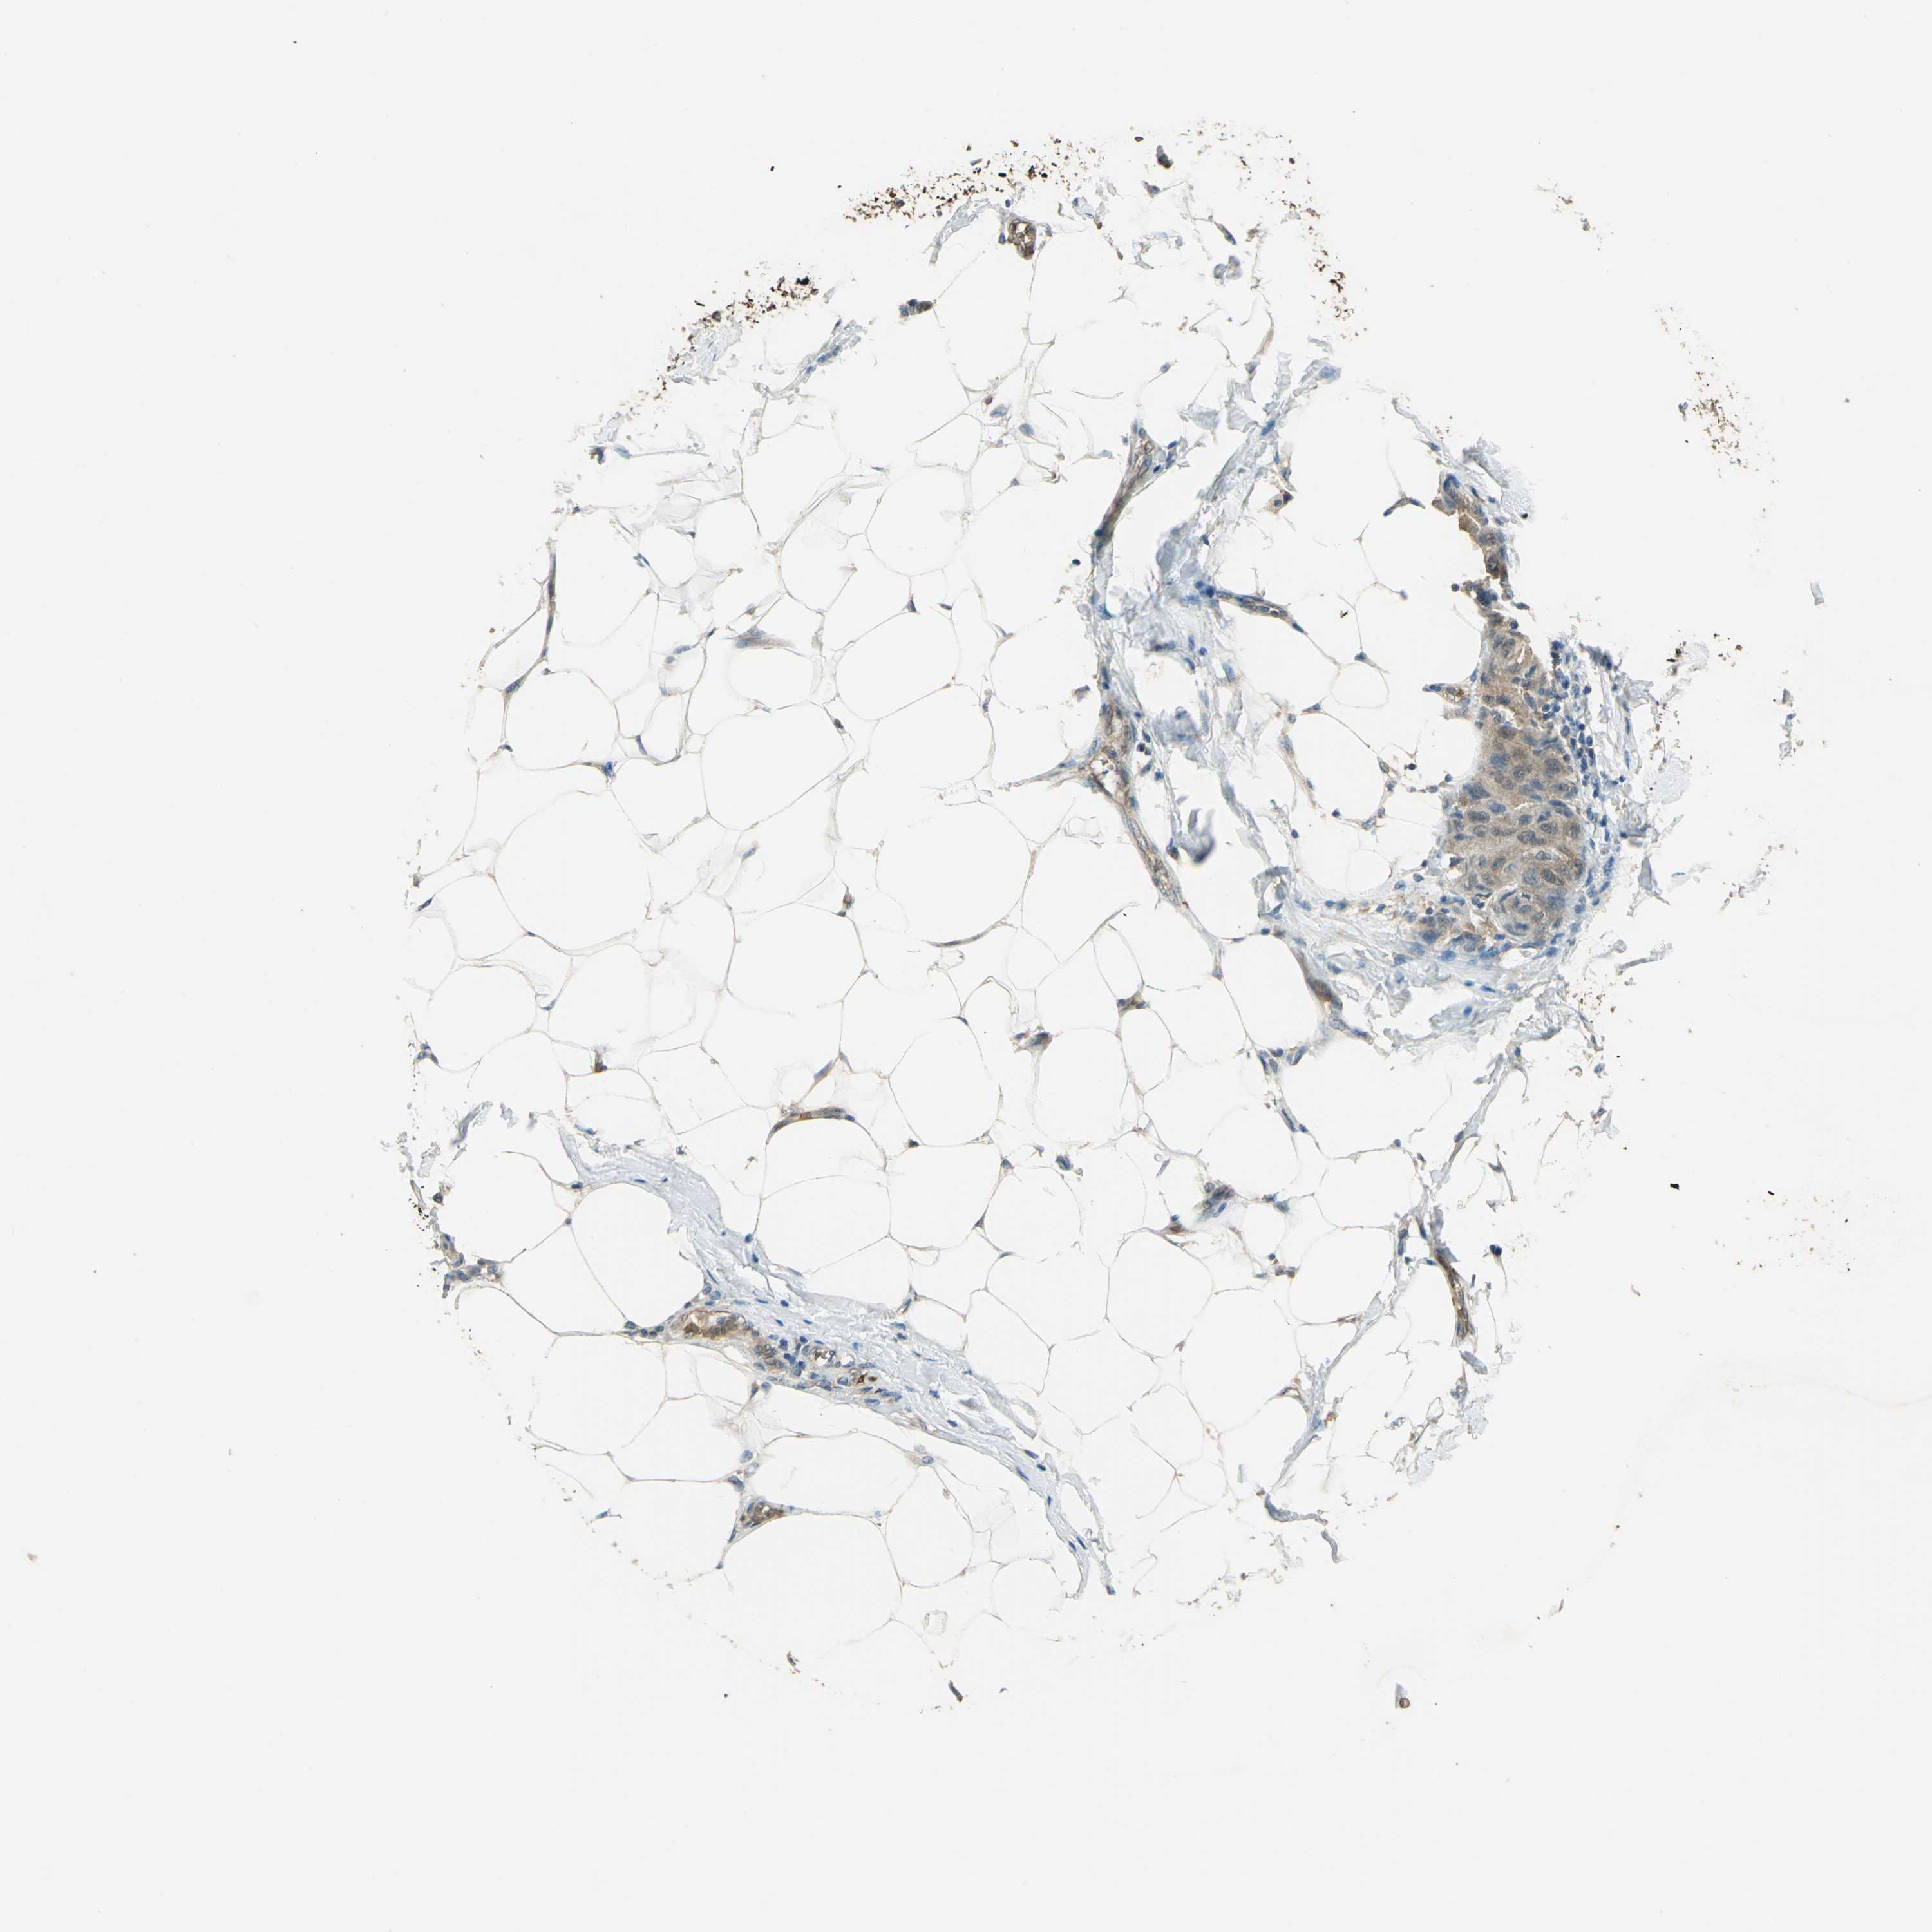

CANCER BREAST CANCER Show tissue menu

BRCA TCGA BRCA VALIDATION PROTEIN EXPRESSION

ANTIBODIES

AND

VALIDATION